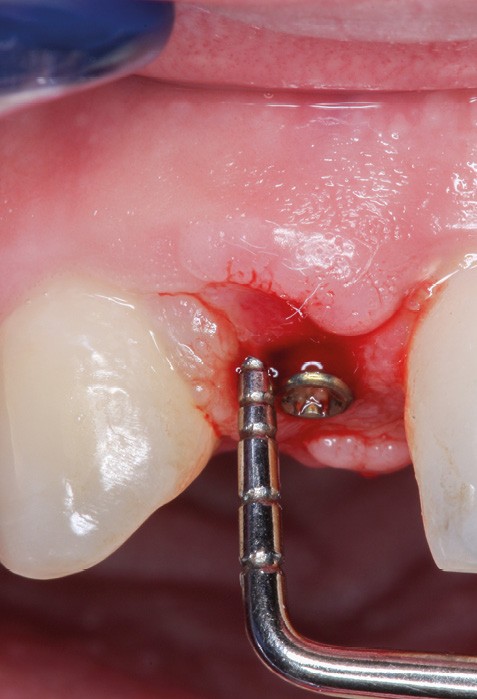

Le nombre d’implants influe aussi sur la survenue de péri-implantite. Dans les reconstructions plurales, l’implant médian est plus à risque de perte osseuse marginale et de péri-implantite [17] (fig. 6 et 7).